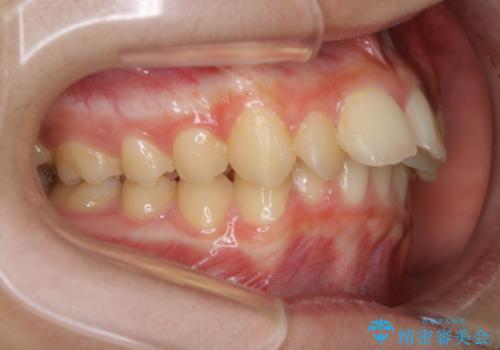

ひと口に出っ歯(上顎前突)といっても原因は多様です。

骨格的な問題があるのか、歯だけの問題なのか、上顎が出ているのか、下顎が出ているのか。あるいはその両方か。

きちんと原因を見極めたうえで治療を開始しないと仕上がりは理想的になりません。

矯正検査を行い、しっかりと矯正診断を行った上で治療を開始することが大事です。